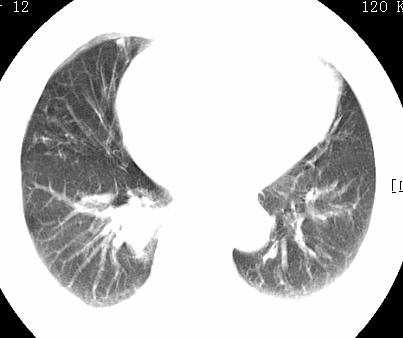

标题: CT26680:肺部右下肺静脉干结节的界定 [打印本页]

标题: CT26680:肺部右下肺静脉干结节的界定

经追查说有支扩咯血病史,但不确定

考虑1、周围型肺癌,2肺静脉畸形,前者可能大,建议增强检查。

考虑1、周围型肺癌,2肺静脉畸形,前者可能大,建议增强检查。支持!

不排除右肺下叶周围型肺癌可能。